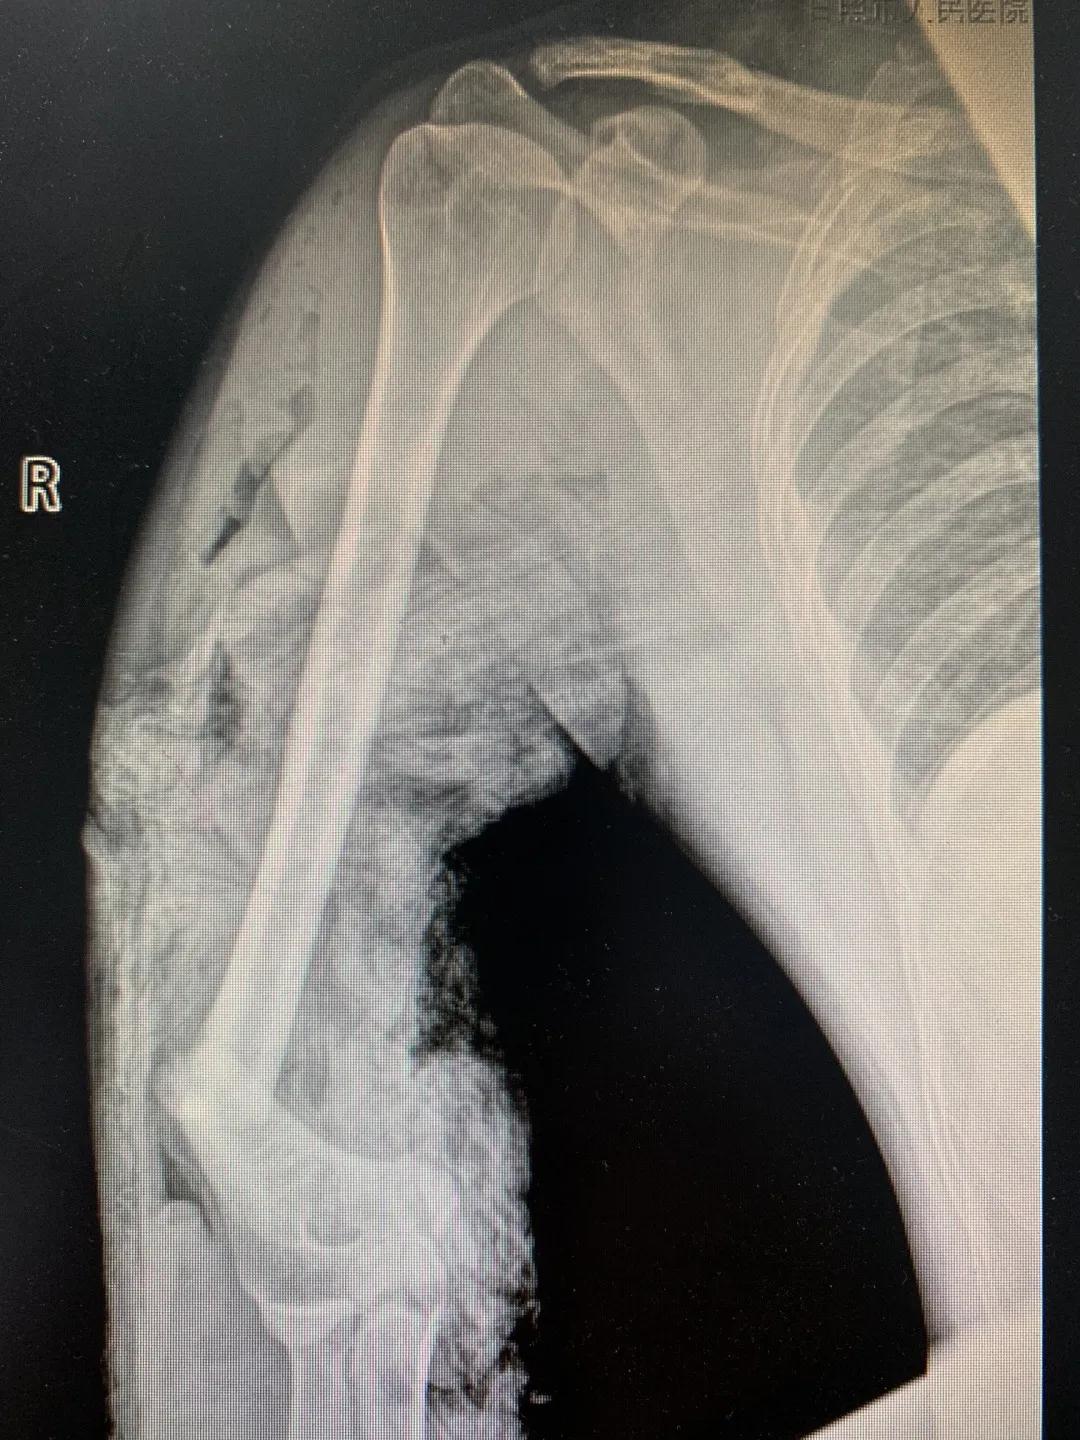

“不仅是个超高难度手术,更是个太棘手的案例!”市人民医院骨科二病区主任苑芳昌第一时间对病例进行了研究:刘某右上肢、胸壁、肩部……整个皮肤的三分之二是缺失的,即便是完好的部分也已经与组织脱落,“如果创面出血得不到控制,马上会失血性休克,开启绿色通道!”

“正常的肢体都有皮肤保护着,如果没有皮肤,我们的肌肉、血管、神经、骨骼露在外面,都会发生坏死。”苑芳昌介绍,伤者的情况非常复杂,伴有多发骨折、肱骨骨折、骨关节的多发错位,还有腕部的骨折,更有血管、神经损伤。不仅如此,伤者右臂在机器里面受到绞伤,肌肉也已经大面积挫伤,各种复杂情形交织在一起甚至让手术“无从下手”。